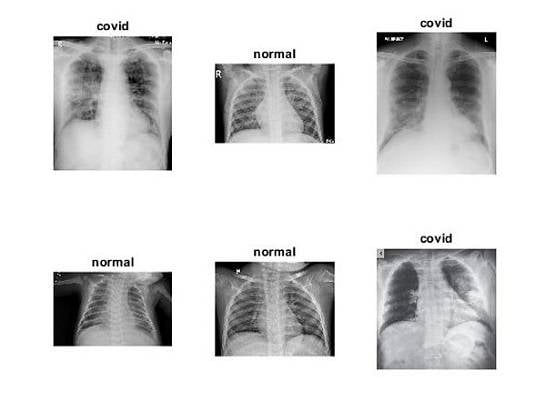

यूनिवर्सिटी ऑफ डेटॉन रिसर्च इंस्टिट्यूट के एक वैज्ञानिक बराथ नारायणन का कहना है कि उनका यह सॉफ्टवेयर  कोड इंसान की चेस्ट को स्कैन कर शरीर में छिपे वायरस का पता लगा सकता है.

इतना ही नहीं, नारायणन का यह भी कहना है कि शरीर में छिपे वायरस के बारे में यह सॉफ्टवेयर 98 प्रतिशत तक सही चीजें बताने में सक्षम है. उन्होंने डेली मेल को एक ई-मेल कर इसका दावा किया है.

नारायणन का कहना है कि यह विशेष सॉफ्टवेयरस सामान्य एक्स-रे स्कैनिंग मशीन से एकदम अलग है. इसे आर्टिफिशियल इंटेलिजेंस (एआई) तकनीक से जोड़ा गया है जिसका रिजल्ट 98 से 99 प्रतिशत तक सही हो सकता है.

बता दें कि नारायणन पिछले काफी समय से आर्टिफिशियल इंटेलिजेंस तकनीक पर काम कर रहे हैं, ताकि डॉक्टर्स ज्यादा तेजी से मरीज की बीमारी को पहचानकर उनका इलाज कर सकें.

इससे पहले उन्होंने ब्रेस्ट कैंसर, मलेरिया, ब्रेन ट्यूमर, ट्यूबरक्लोसिस, डायबिटीज और निमोनिया जैसी बीमारियों का तेजी से पता करने के लिए सॉफ्टवेयर कोड्स इजाद किए हैं.